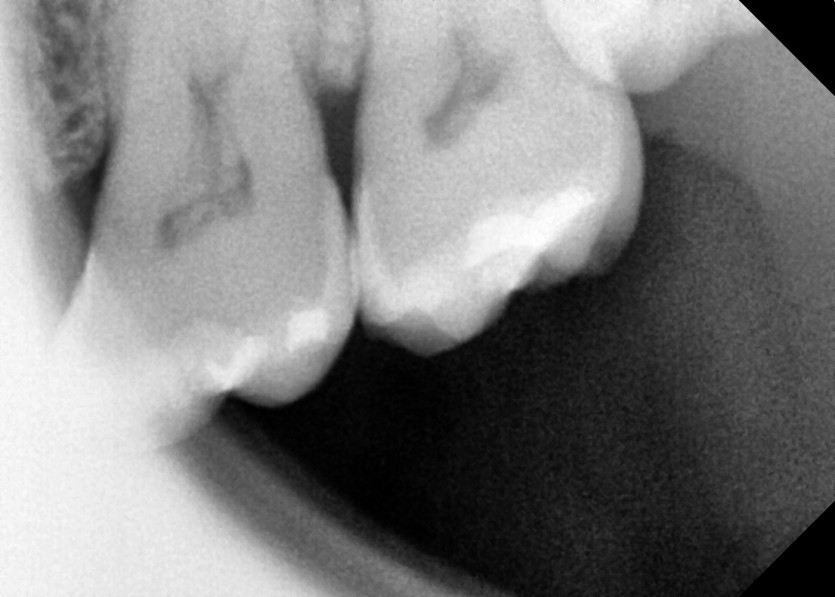

#28,38,48 사랑니 발치

구강 외과 전문의가 당일 발치했습니다.